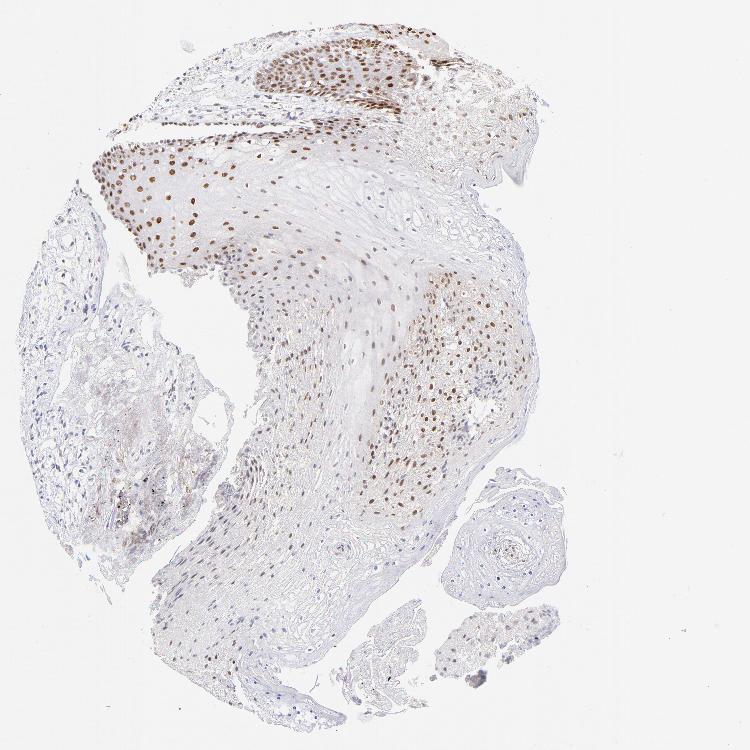

TISSUE PRIMARY DATA ORAL MUCOSA Show tissue menu

ORAL MUCOSA - Antibody stainingi

Antibody staining in the annotated cell types in the current human tissue is reported as not detected, low, medium, or high, based on conventional immunohistochemistry profiling in selected tissues. This score is based on the combination of the staining intensity and fraction of stained cells.

Each image is clickable and will lead to virtual microscopy that enables deeper exploration of all samples and also displays staining intensity scores, fraction scores and subcellular localization as well as patient and tissue information for each sample.

Antibody HPA002926

Squamous epithelial cells High